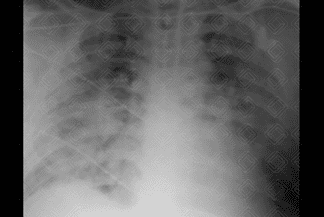

Descrição das figuras 4, 5, 6 e 7: Radiografia e nova tomografia de tórax, realizadas 4 dias após admissão, evidenciando piora dos achados pulmonares. Importante aumento das opacidades em vidro fosco periféricas.

• Opacidade e/ou consolidações bilaterais, acometendo grande parte dos lobos pulmonares, com predomínio na periferia dos pulmões;

• Achados poucos específicos e de difícil caracterização na radiografia convencional.